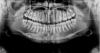

Bier Опубликовано 29 октября, 2009 Поделиться Опубликовано 29 октября, 2009 Докторам: Я что один вижу на снимке приличный дефект костной ткани в области 21 зуба? 1. в личке2. мостовидный протез с опорой на 12,11,22 зубы. Внизу отдельные коронки.3. Я решительно против системы Bicon, Нобель вполне подходит, но и помимо Нобеля есть еще масса хороших систем.4.Про костную пластику вы что-то не так поняли. Она нужна чтобы было куда закручивать имплантат. Нагрузка тут ни при чем. Сфотографируйте во рту у ребенка эту зону без протеза, будет понятнее. Ссылка на комментарий

Андрей Опубликовано 29 октября, 2009 Поделиться Опубликовано 29 октября, 2009 Докторам: Я что один вижу на снимке приличный дефект костной ткани в области 21 зуба? Да дефект там приличный, если это конечно не снимок сразу после удаления. Ссылка на комментарий